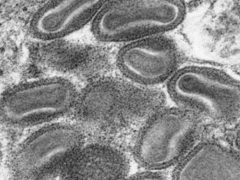

ウシ(牛)の病気  ウイルス

ウイルス  ウイルス

ウイルス  ウイルス